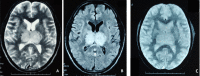

A 35-year-old man with a history of multiple substances abuse (alcohol, tobacco and cannabis) presented with acute, severe, holocranial headache associated with nausea and few episodes of vomiting followed by acute onset Broca-type aphasia with intact comprehension from next day, without any other focal neurodeficits, seizure or altered sensorium. Neurological examination was marked by Broca-type aphasia and failure in convergence reaction bilaterally, rest unremarkable. Brain imaging revealed lesions in bilateral thalamus, while magnetic resonance venography showed multiple flow voids in posterior part of superior sagittal sinus and bilateral transverse sinus. A diagnosis of cerebral venous sinus thrombosis was made. Subsequent investigations revealed decreased levels of protein C, protein S and antithrombin III. The patient was started on anticoagulation to which his headache and aphasia recovered completely after 8 and 12 days of therapy, respectively. He is being continued on anticoagulation and is following-up with us for past 4 months uneventfully.